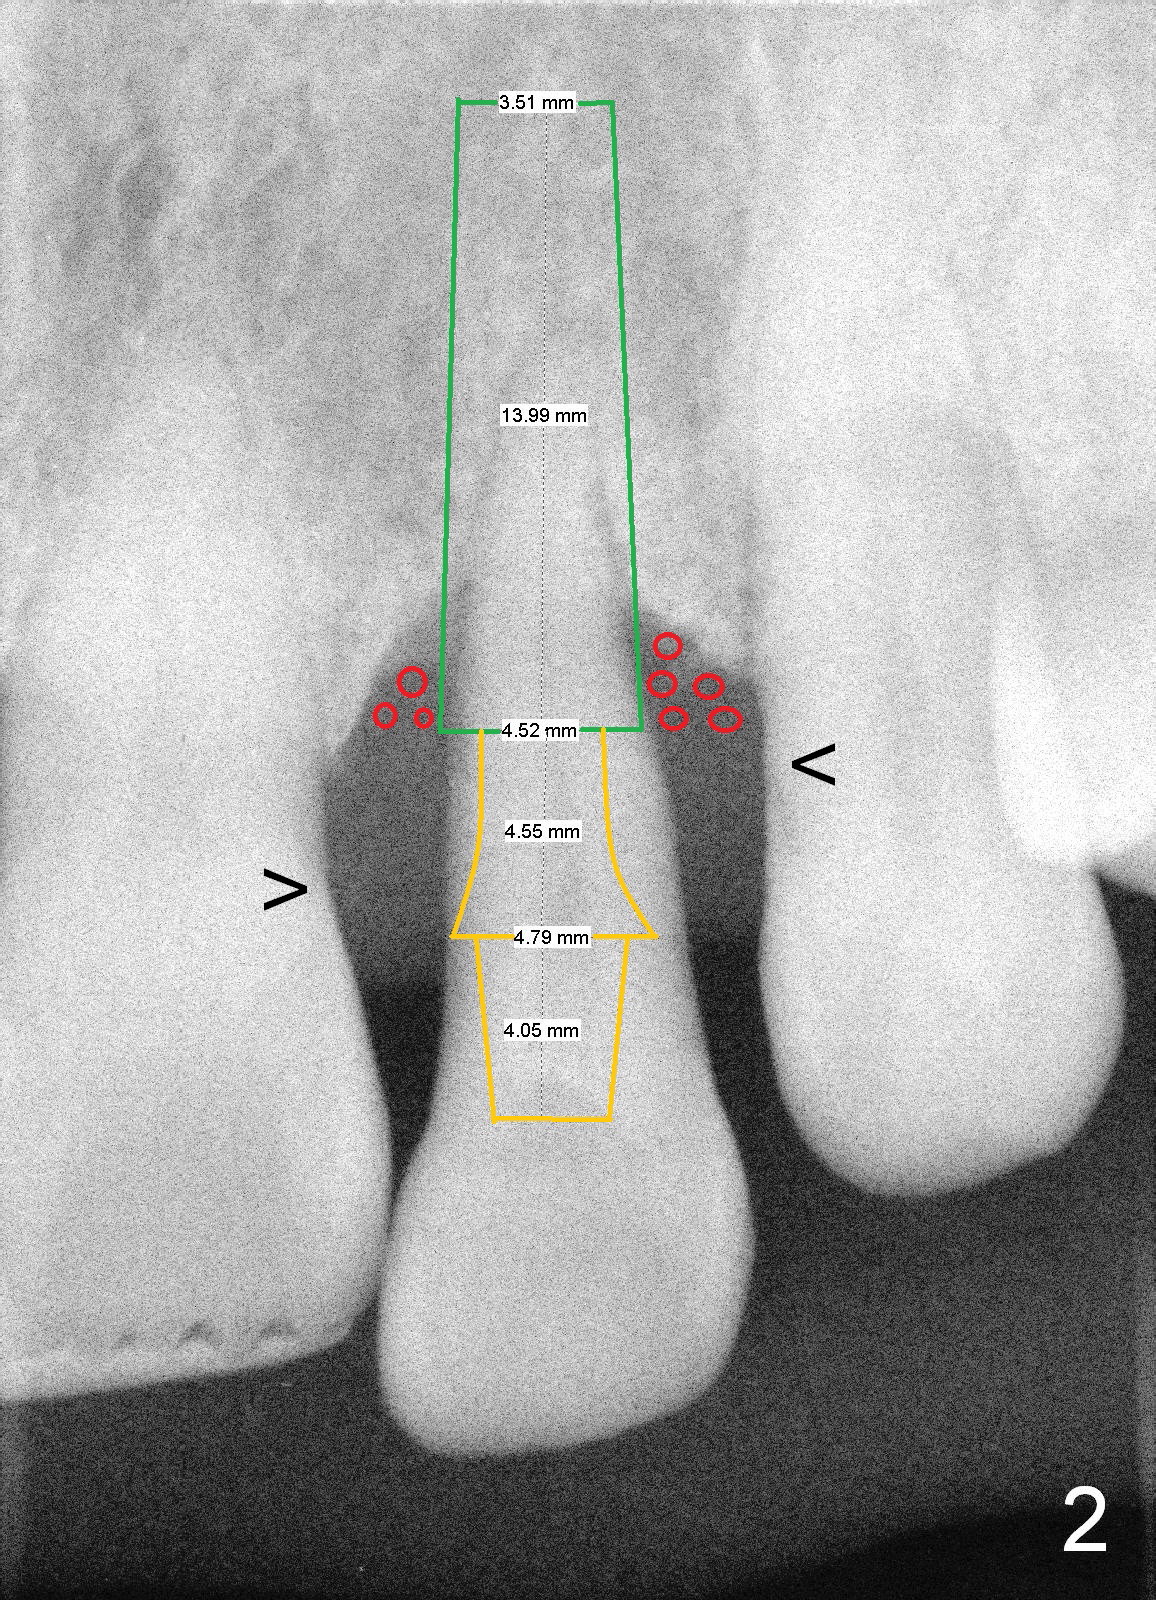

A 46-year-old lady has severe chronic periodontitis. The tooth #10 has drifted inferiorly and labially (Fig.1). One month and a half after #31 immediate implant, she wants to take care of #10. After extraction, measure the socket and tooth dimension. The implant (green box in Fig.2) diameter should be at least 2 mm smaller than the buccopalatal width of the socket. The platform of the implant should be 2-3 mm superior to the CEJ (cementoenamel junction (arrowheads)) of the neighboring teeth. The exposed implant threads will be covered by bone graft (red circles). Since the gingiva is thick (coronoapically), the abutment (gold color) cuff is expected to be 3-4 mm.

If the labial gingiva is thick (buccopalatally), a cemented abutment is chosen to support an immediate provisional. Otherwise, a temporary abutment will be used. It is reported that the temporary abutment promotes gingival growth. Which abutment is chosen?